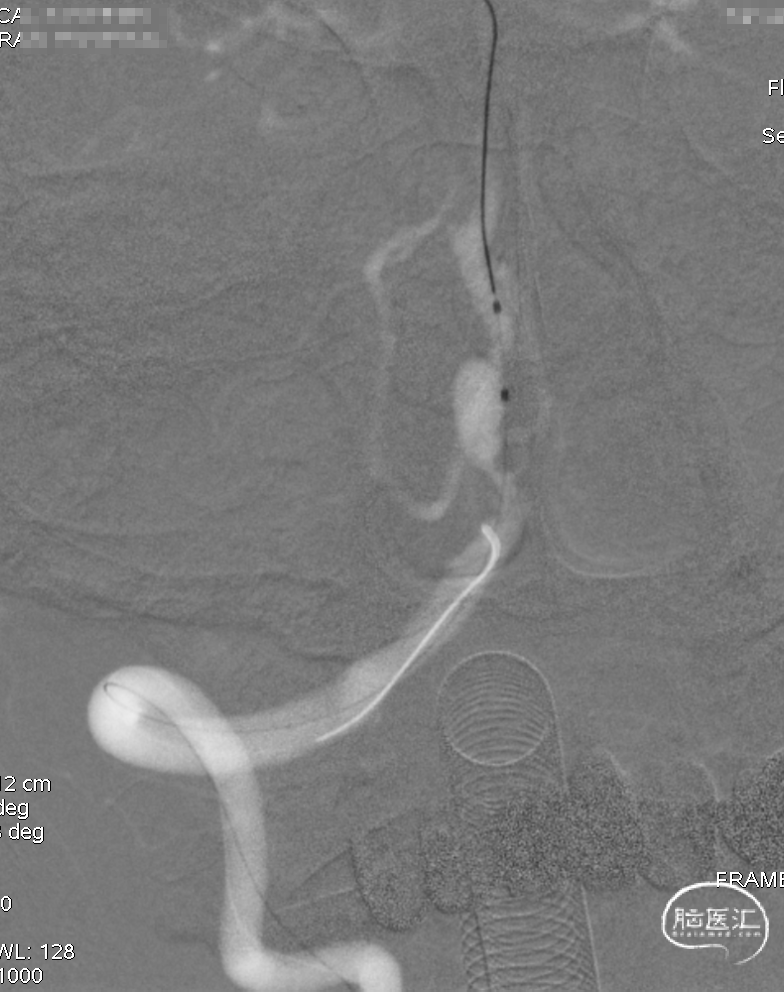

银蛇DA到位

Roadmap

通桥白驹®球囊(2.5*10),先远后近扩张。

球扩后,狭窄改善。

Marksman到位。